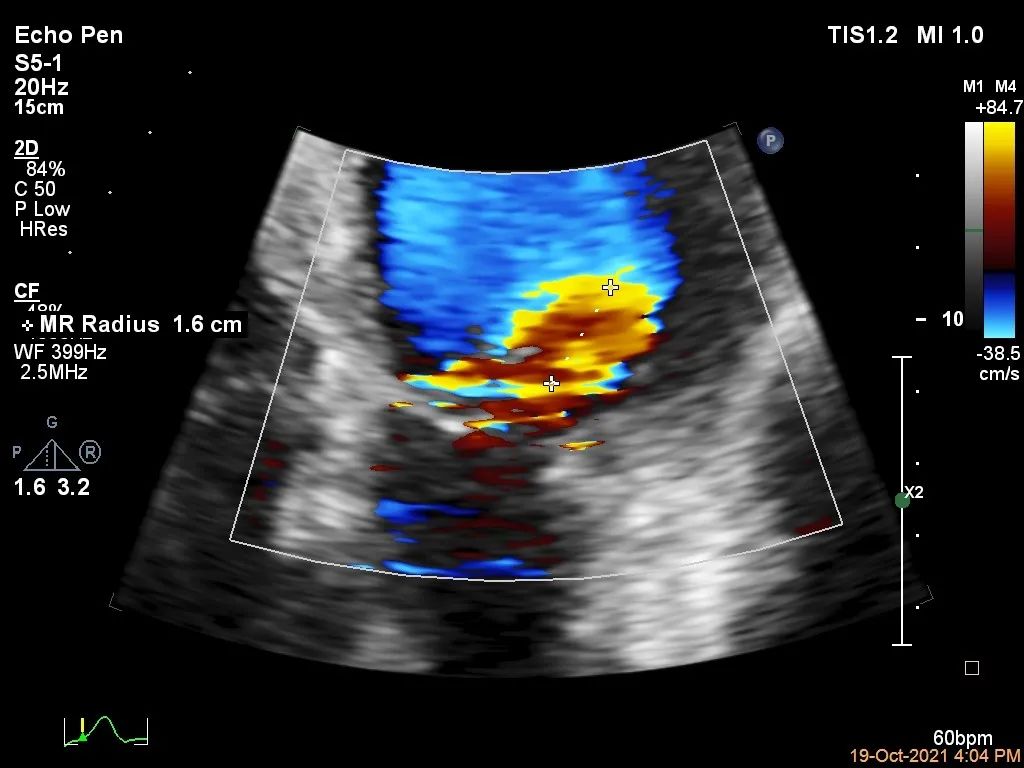

Bicom:MR(重度),反流束宽22mm,反流面积24.2cm²,PISA法定量EROA:2.3cm²,Rvol:274ml,RF:57%,r:16mm。

二尖瓣反流频谱呈全收缩期

肺静脉血流频谱呈收缩期反向